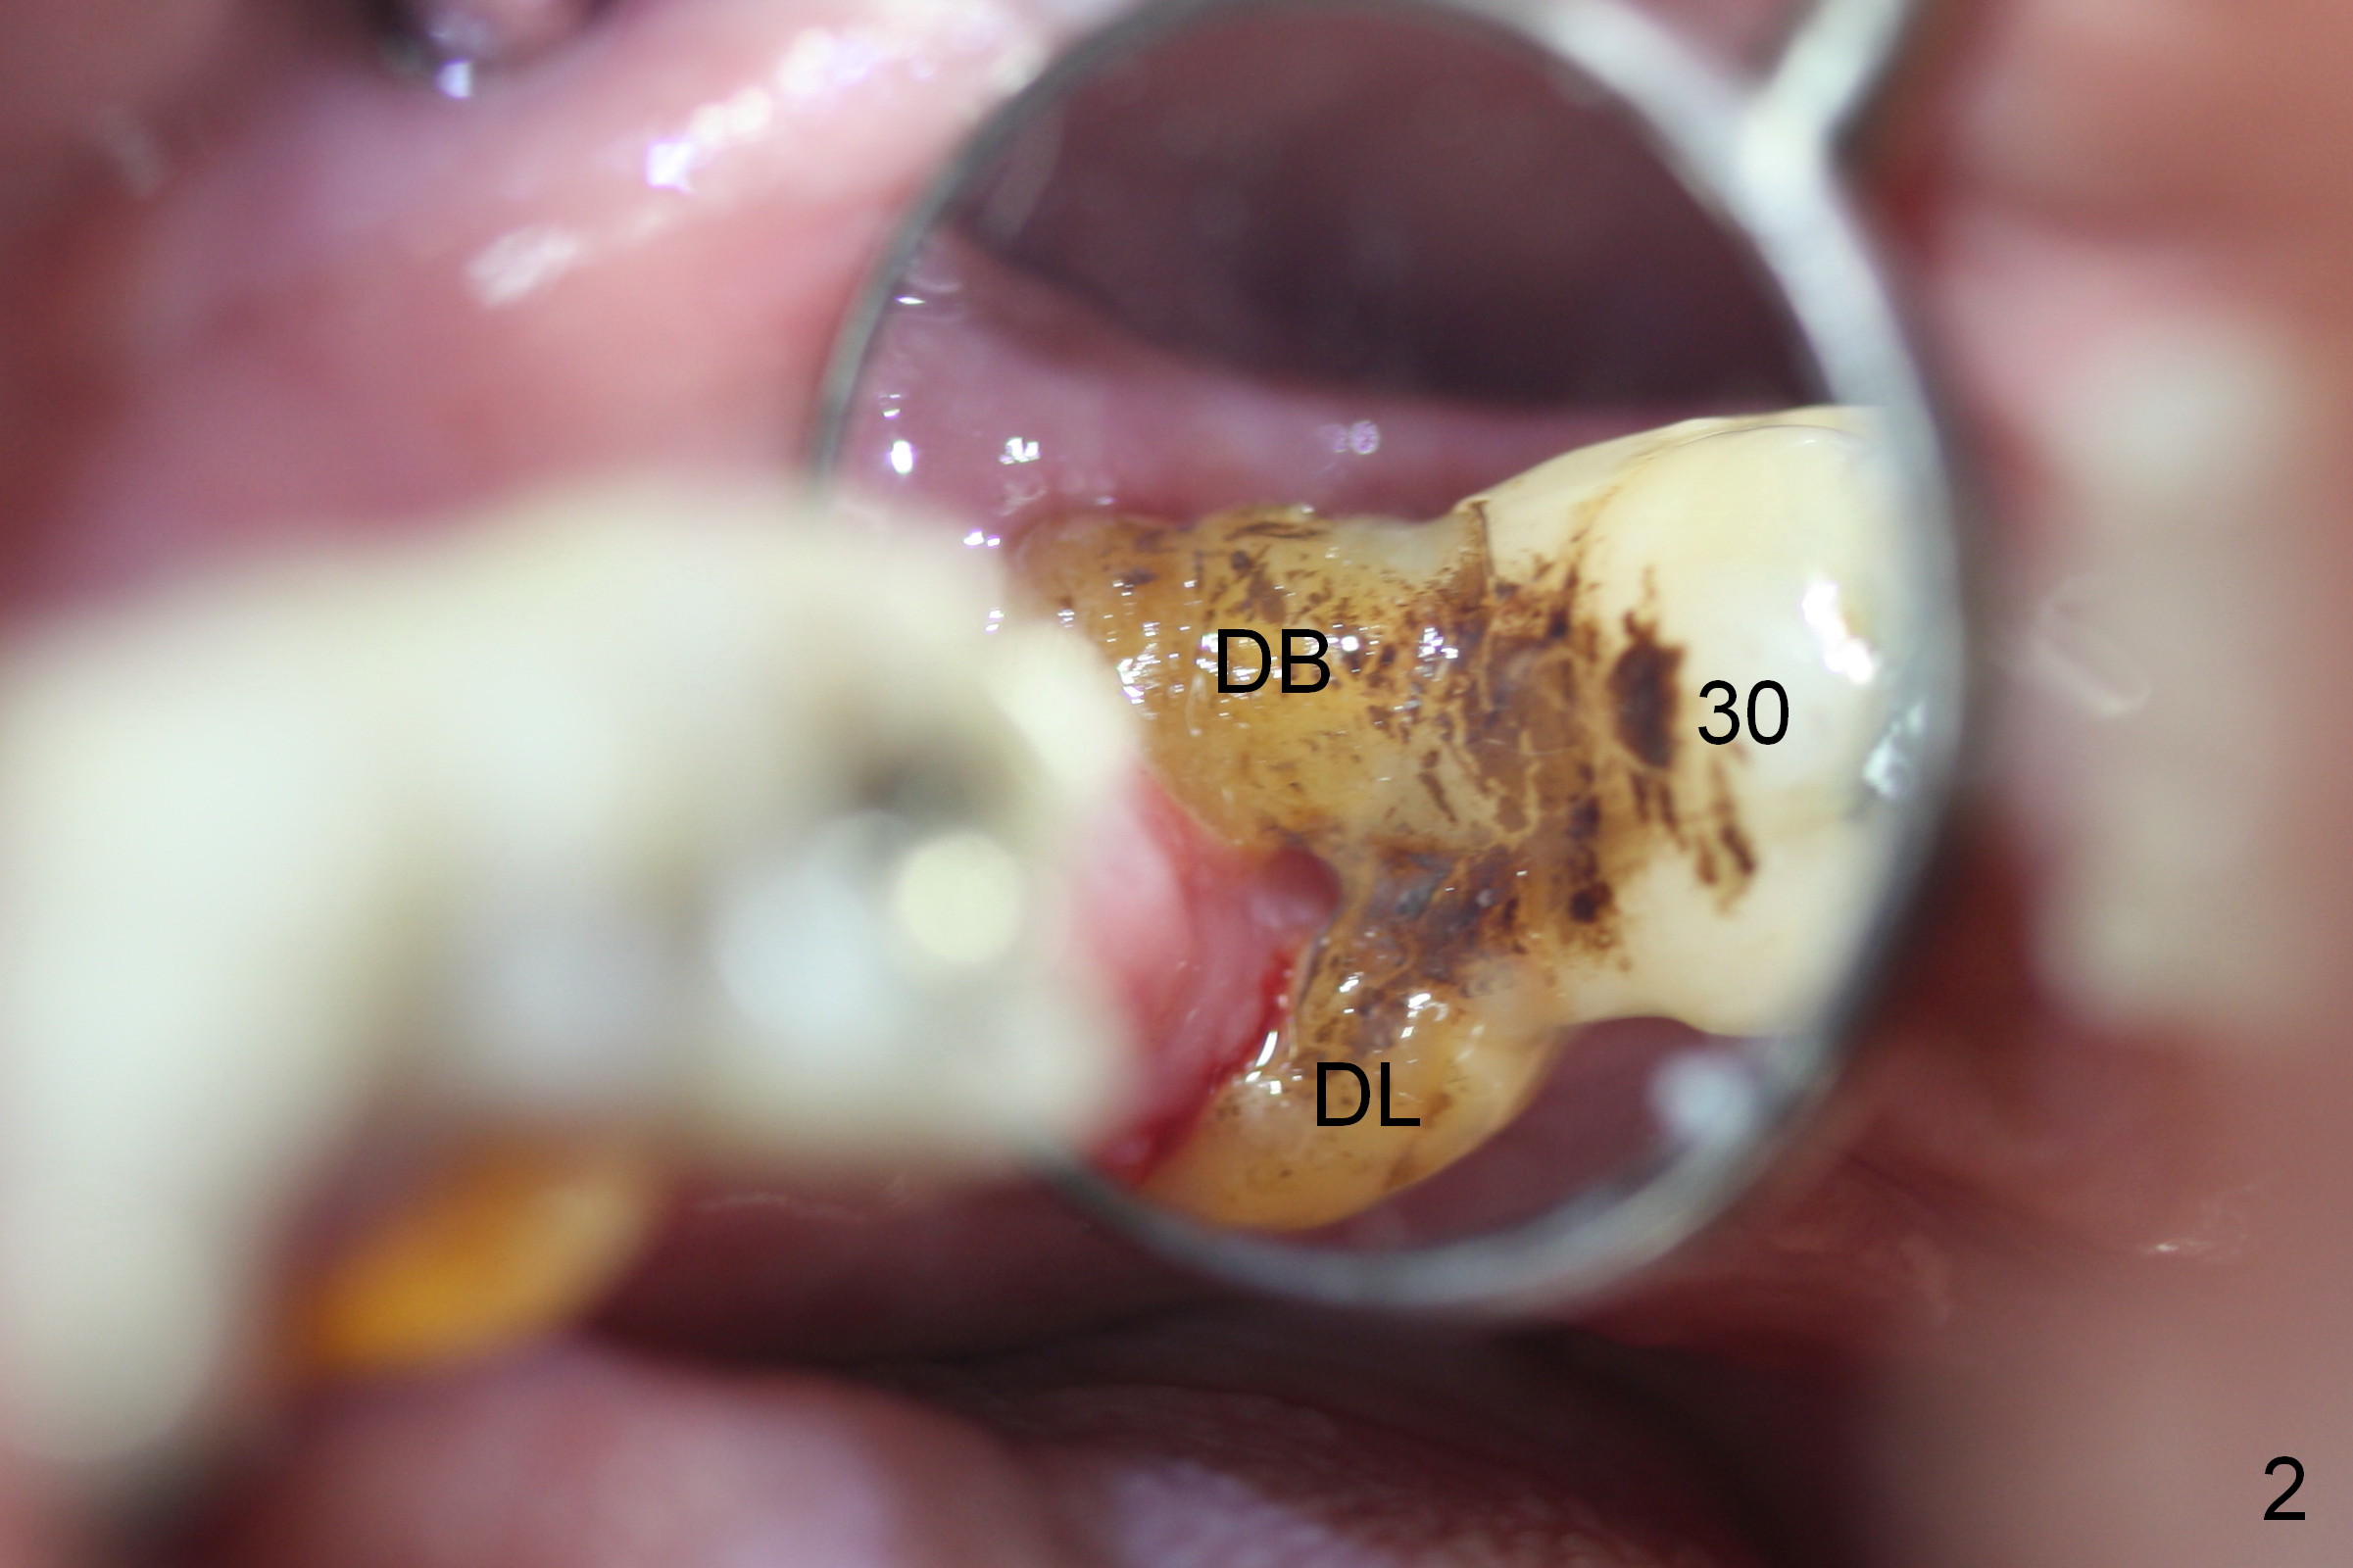

A 74-year-old man requests the 5th implant placement at #30.  He feels that immediate implant (1,2) is associated with less pain than delayed one.  He is looking forward the immediate implant at #30.  This tooth has severe gingival recession (Fig.1,2): the mesial (M), distobuccal (DB) and distolingual (DL) roots having been exposed.  The socket with the tripod septum will be treated with Metronidazole, randomly selected by case sequence.  One of challenges to implant placement is to handle keratinized (K) and non-keratinized (N) gingival tissues.  After tooth removal and infection resolution, it is expected that some of non-keratinized tissue can be converted to the keratinized one to promote health of the implant.  Fabricate a tightly fit immediate provisional to cover the irregularly-shaped socket.  Use a nonresorbable membrane where the provisional is unable to cover the socket.  Preop PA is to be taken for design.  Bone height should be limited.